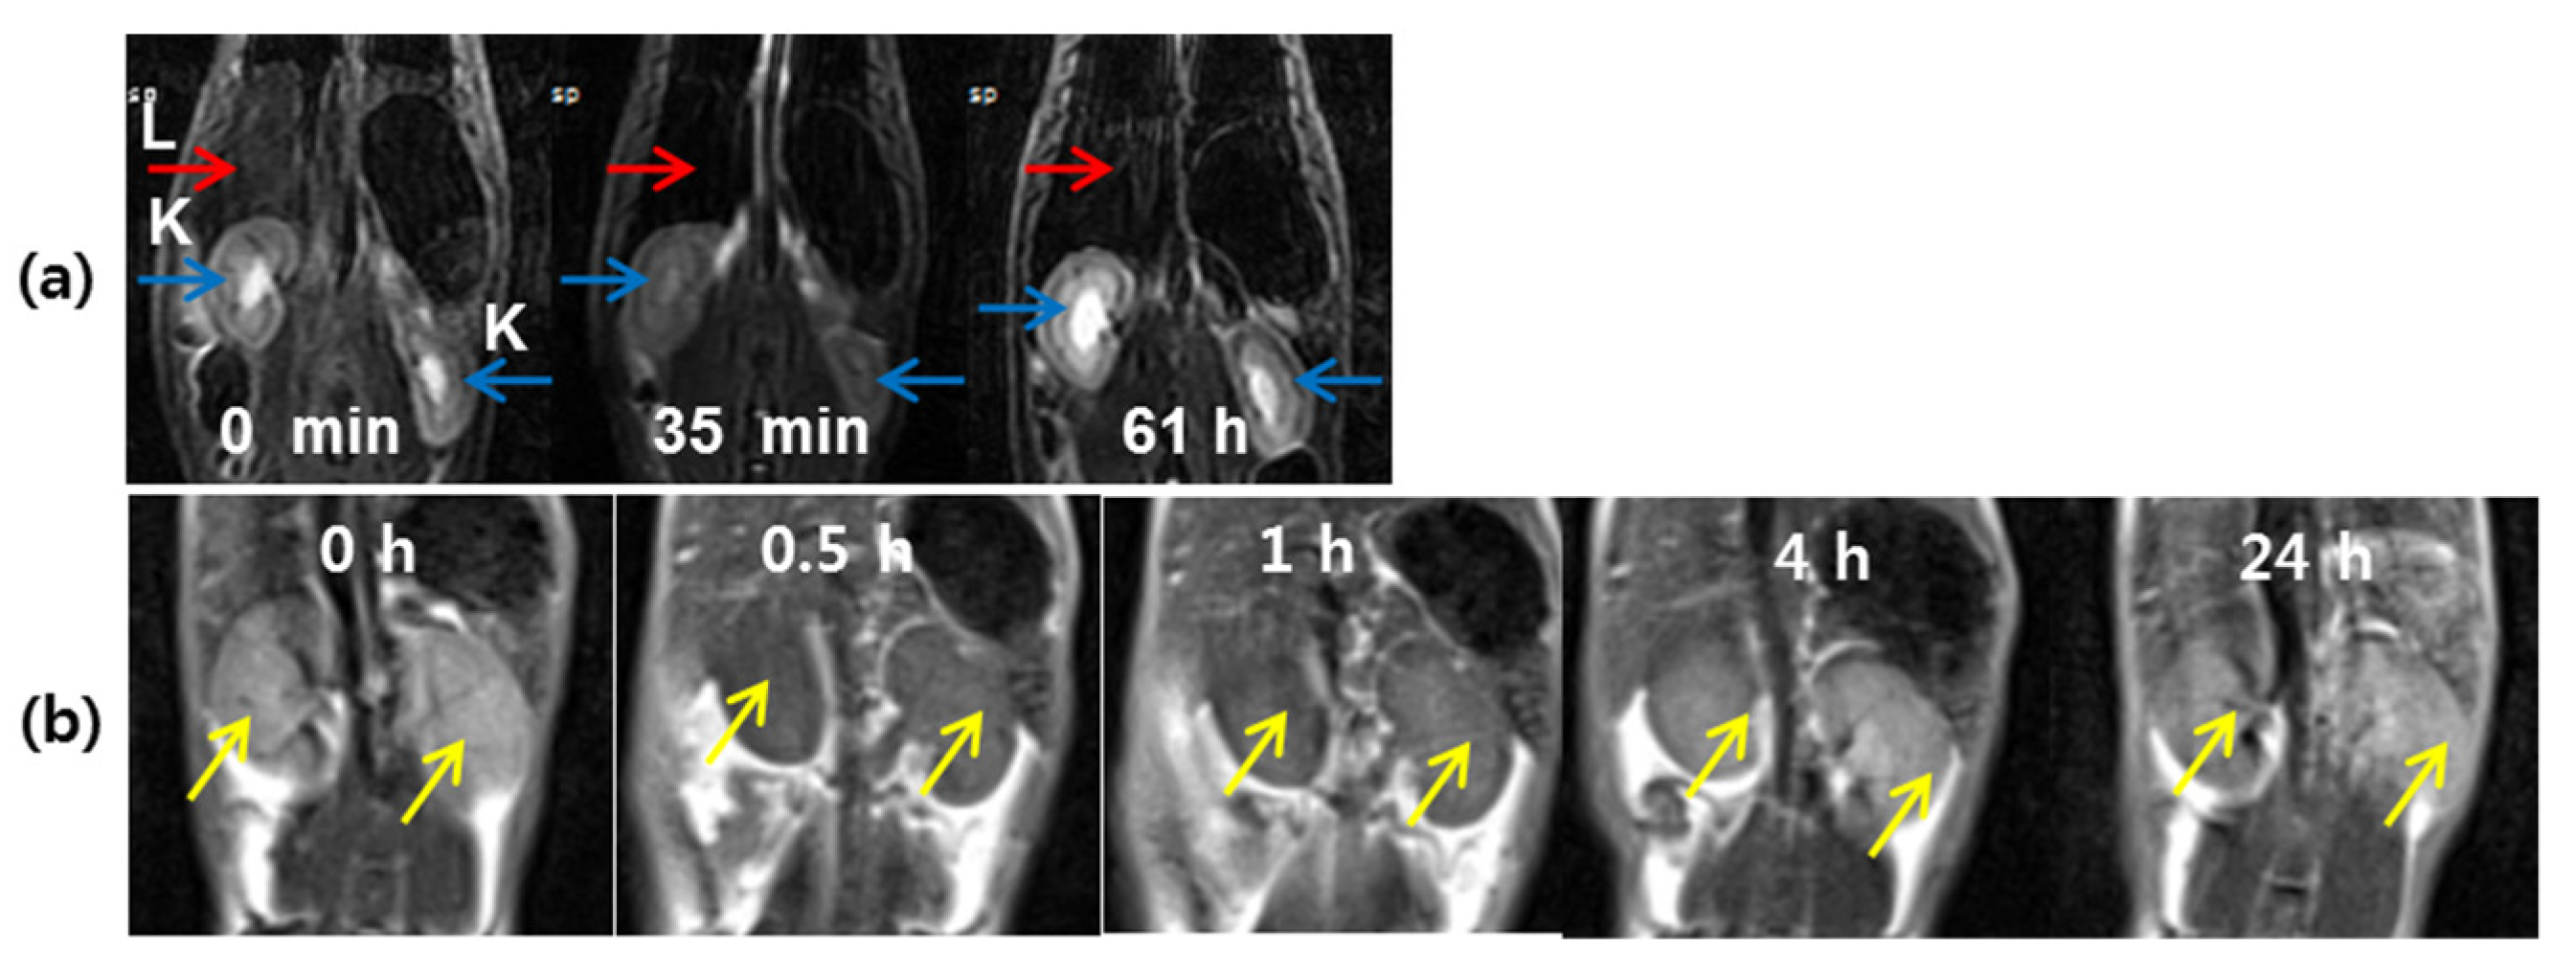

- Ho, S.L.; Cha, H.; Oh, I.T.; Jung, K.-H.; Kim, M.H.; Lee, Y.J.; Miao, X.; Tegafaw, T.; Ahmad, M.Y.; Chae, K.S.; et al. Magnetic resonance imaging, gadolinium neutron capture therapy, and tumor cell detection using ultrasmall Gd2O3 nanoparticles coated with polyacrylic acid-rhodamine B as a multifunctional tumor theragnostic agent. RSC Adv. 2018, 8, 12653–12665. [Google Scholar] [CrossRef] [Green Version]